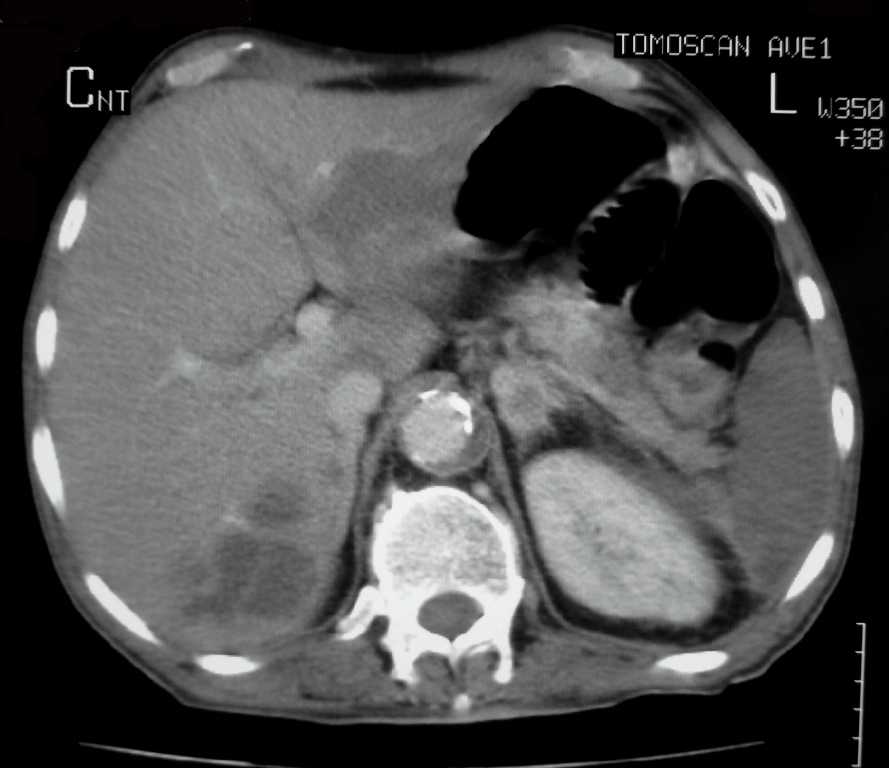

We describe the case of a 60-year-old diabetic man who was admitted to our hospital with keto-acidosis and rapidly developed sepsis and a mycotic abdominal aortic aneurysm (AAA) with branch involvement. Early and late findings on serial computed tomography (CT) examinations are presented. Awareness and recognition of early imaging findings associated with infectious aortitis and serial CT examination in cases of patients with sepsis and predisposing factors are essential for prompt diagnosis and treatment.